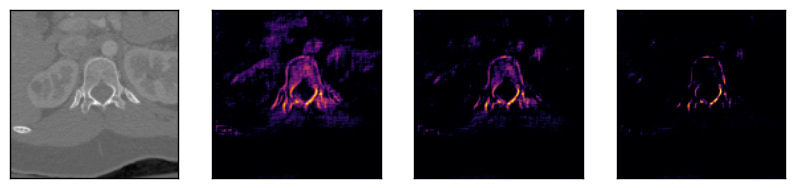

Some segmentation results at different vertebrae (top) and liver (bottom) areas are depicted in Fig. 2. The red contour corresponds to the outline of the prediction, green to the ground-truth and yellow to the overlap of the outlines.

IV-E Visual feature inspection

In order to visually demonstrate the sequential nature of the features learnt by our model, we performed the following test. We passed two sequences to the network (both for vertebrae), each containing three identical slices (first column in Fig. 3). The columns show some of the features extracted after the penultimate upsampling step (after layer in Table I) before passing them to the final bidirectional C-LSTM block. The visualization shows that the layers respond differently to the same input element, activating different parts of the organ of interest. The brighter colour intensities correspond to higher activations. Comparing the rows, it shows that the network is able to learn spatial correlations in both directions.